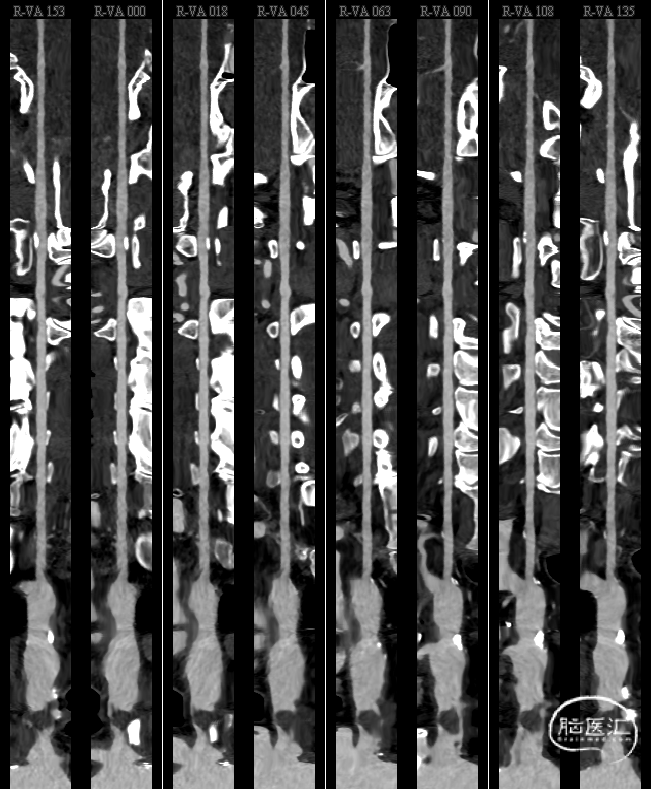

继续筛查颅外段血管完善颈部血管CTA:可见头臂干钙化斑块,伴低密度影,考虑附壁血栓。

复查颈部血管CTA提示血栓较前明显减小。

抗凝一周后复查颈部血管CTA,血栓明显减小,血栓附着于头臂干左前侧壁。